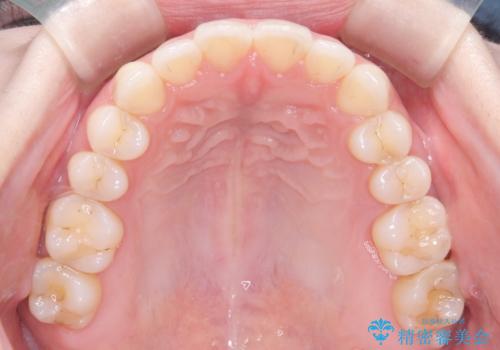

- 前歯の凸凹を主訴に来院された患者様です

骨格性の下顎前突傾向もあったため、臼歯関係の遠心移動も行うことで綺麗な仕上がりで矯正を終了することができました。

遠心移動を行うことで期間はかかりましたが、良い状態で仕上がっています。